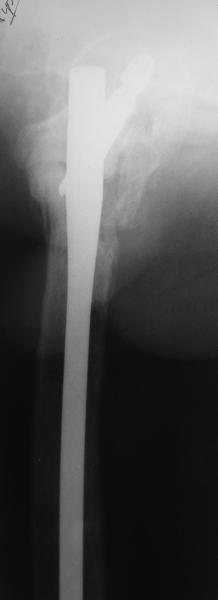

В приложении пример пациента, близкого по картине к тому, что представил Виктор (варус и смещение периферического отломка на поперечник кзади). Сделали как раз то, что Виктор исходно намеревался - аппаратная коррекция и затем гамма.